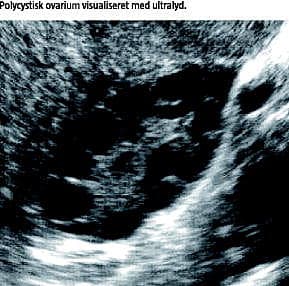

De i dag anvendte diagnostiske kriterier for PCOS (Tabel 1 ) blev udfærdiget af The Rotterdam ESHRE/ASRM-Sponsered Consensus Workshop Group 2003 som et kompromis mellem den tidligere foretrukne europæiske diagnostik med hovedvægt på ultralyd og de diagnostiske principper i USA, hvor man tilskrev kronisk anovulation og biokemiske ændringer større klinisk betydning [3].

Mange mekanismer i udviklingen af PCOS er endnu ikke klarlagte. Overordnet set kan hyperinsulinæmi (HI) samt en lokal IR i ovarierne forklare den øgede ovarielle androgenproduktion og dermed udviklingen af de kliniske manifestationer i syndromet [3]. HI virker synergistisk med lutiniserende hormon (LH) under stimulation af theca-cellernes androgensyntese, hvorved den ovarielle sekretion af androstendion og testosteron øges. Endvidere hæmmes syntesen af det kønshormonbindende globulin (SHBG), hvilket medfører en stigning i frit cirkulerende androgen. Øget udskillelse af LH fra hypofysen opfattes som en kompensatorisk følge af en nedsat ovariel LH-effekt pga. lokal IR i ovariet og en androgeninduceret desensibilisering for progesteron på hypotalamus/hypofyseniveau. På denne måde øges LH/follikelstimulerende hormon (FSH)-ratio, og i samspil med det abnorme intraovarielle endokrine miljø dannes det øgede antal umodne (præantrale) follikler i ovarierne [5] (Figur 1 ).